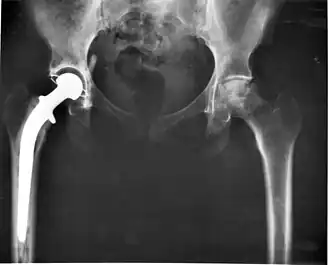

Prothèse totale de hanche

Une prothèse totale de hanche (PTH) est un dispositif articulaire interne qui vise à remplacer l'articulation de la hanche et lui permettre un fonctionnement quasi normal, en tout cas permettant la marche.